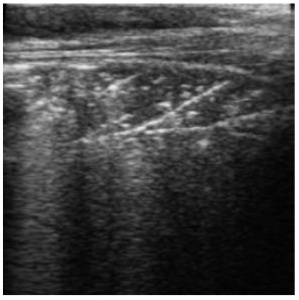

Comet tailing describes the shapes seen on the ultrasound image caused by fluid or gas bubbles. These occur when the ultrasound pulse bounces off fluid or gas bubbles and returns to the probe.

Ultrasound appearance

Score 0 – Healthy, aerated lungs

Score 2 – Small areas of consolidation

Score 3 – Larger areas of consolidation